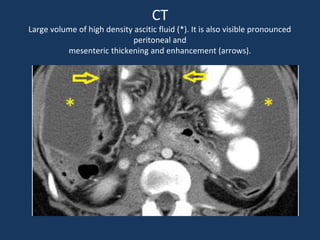

CT

Large volume of high density ascitic fluid (*). It is also visible pronounced

peritoneal and

mesenteric thickening and enhancement (arrows).

CT Large volume ofhigh density ascitic fluid (*). It is also visible pronounced peritoneal and mesenteric thickening and enhancement (arrows).